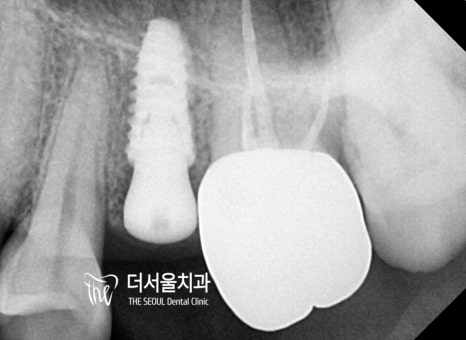

계산된 위치에 픽스처를 심어드렸습니다.

다행히 올곧게 잘 심어져 있는 모습이네요ㅎㅎ

더서울에서는 약 몇 달간

골융합 정도를 확인한 뒤에

최종 보철을 올려드리기로 했습니다.

지르코니아로 제작된 크라운을

구강 내에 세팅한 모습입니다.

옆에 있는 소구치와 크기, 형태

모든 게 잘 어우러지고 있는 모습인데요.